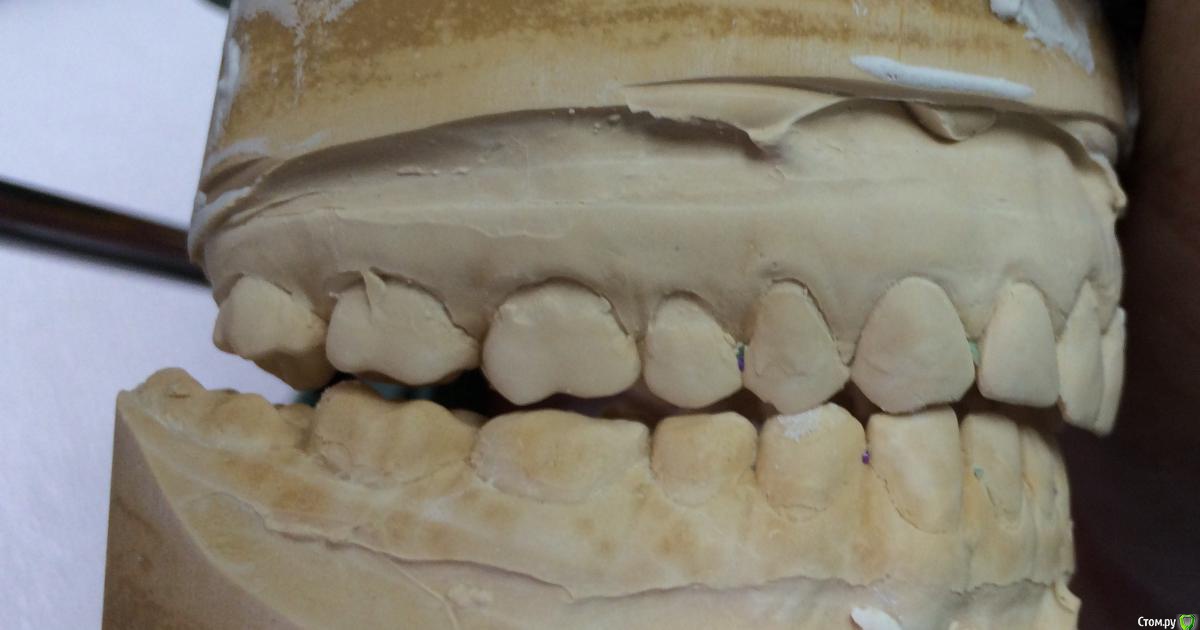

Larnary Опубликовано 28 июля, 2015 Поделиться Опубликовано 28 июля, 2015 (изменено) Добрый день!Ко мне обратилась пациент 1988 гр с жалобой на стираемость зубов и постоянные сколы пломб.Объективно небная поверхность верхних резцов стерта до дентина. Окклюзионная стираемость жевательной группы зубов.Прошу помочь с выявлением причины такой стираемости зубов и оптимальноно метода лечения Изменено 28 июля, 2015 пользователем Larnary Ссылка на комментарий

Larnary Опубликовано 28 июля, 2015 Автор Поделиться Опубликовано 28 июля, 2015 (изменено) Видно окклюзионнык интерференции в области 37 и 47.На днях удален 38 и дальше будут удалены остальные восьмерки. На ТРГ мне видится небольшая ретрузия верхних резцов,дистальный прикус. Так же левпя окклюзионная кривая более выраженная,чем правая Изменено 28 июля, 2015 пользователем Larnary 1 Ссылка на комментарий

Bobby Опубликовано 29 июля, 2015 Поделиться Опубликовано 29 июля, 2015 Фасетки стираемости на нёбных поверхностях верхних резцов и вестибулярных поверхностях нижних резцов обусловлены малым оверджетом - недостаточная щель по саггитали, поэтому и будут колоться реставрации, а ткани зубов истираться. Фрадеани про это на своём курсе рассказывал и показывал видео как это диагносцировать и что с этим делать. Что вообще хочет пациентка и на что готова? Эти вопросы лучше сразу решать на первичной консультации, а то делаете диагностики, всё рассчитываете, распинаетесь, а они потом: "ой, я пока не готов/а к такому плану лечения" и всё заканчивается композитной мазнёй в другой клинике. 5 Ссылка на комментарий

Maverick Опубликовано 9 августа, 2015 Поделиться Опубликовано 9 августа, 2015 (изменено) Думаю в данном кейсе интрузия резцов будет нежелательна, десневые контуры фронтальной группы зубов выглядят хорошо, ровно, нет разницы в высоте(если конечно не были внесены изменения в контур десны, типа пластик) . И тут не дентальный глубокий прикус, а скелетный, как было отмечено выше. Еще один негативный момент в интрузии, который играет важную роль , так это искусственное состаривание пациента, верхняя губа имеет свойство опускаться со временем, что только ухудшит картину эстетики улыбки. Экспозиция резцов очень важный критерий в планировании лечения, тут надо отталкиваться от возраста пациента. Думаю у данного пациента, учитывая возраст, позицию фронтальных зубов , уровень десны идеально будет завысить прикус в боковом отделе и вывести в небольшой вестибулярный наклон фронт на брекетах, либо как упоминалось выше за счет изменение наклона коронковой части, путем керамических реставраций, что удобнее для пациента в плане финансовых и временных затрат. P.S. Такое ощущение , что есть определенные проблемы с клыковым ведением, поэтому и интерфреннции возникают в боковом отделе. Поэтому хорошо было бы увидеть все в артикуляторе, чтобы уже точно знать причину Угол межрезцовый идеальный 132 градуса плюс минус 10 град. Изменено 9 августа, 2015 пользователем Maverick 2 Ссылка на комментарий